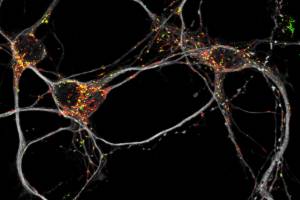

Biowissenschaften - Gesundheit - 28.08.2020

Dank einer Stoffwechsel-Umstellung können diese Zellen trotz Schäden an den Mitochondrien funktionstüchtig bleiben Mitochondrien sind die Kraftwerke unserer Zellen. Speziell Nervenzellen benötigen viel Energie und sind deshalb besonders von diesen Organellen abhängig. Bei verschiedenen vererbten aber auch alterungsbedingten neurodegenerativen Erkrankungen wie zum Beispiel Parkinson können Schäden an den Mitochondrien auftreten.